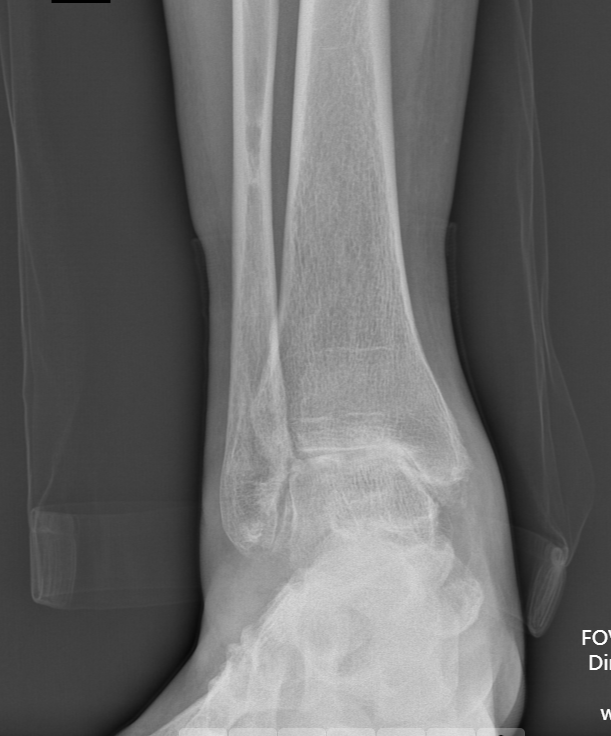

第一台手术的患者是位75岁的叔叔,被“脚脖子”痛缠了4年,疼得越来越厉害,病情已经到了严重阶段。

术前踝关节正位X线

武勇主任团队给他做了3D打印导板辅助下人工全踝关节置换术。

这种手术适合踝关节病严重的患者,通过替换病变的关节结构,能帮着缓解疼痛、恢复关节活动,让老人日常走路更自在些。